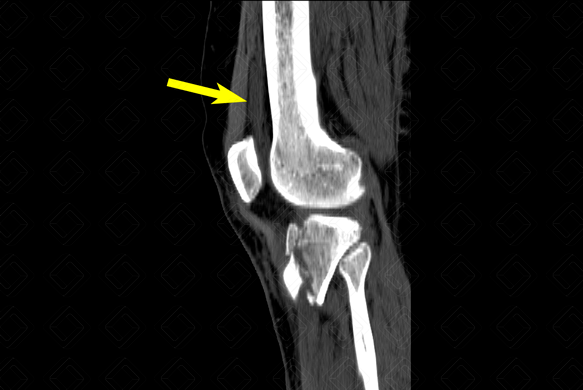

Texto alternativo para a imagem Figura 3. Créditos: Dra. Elazir Mota - Rio de Janeiro/RJ

Descrição das f iguras 2 e 3: Tomografia computadorizada do joelho direito. Fratura do platô tibial bicondiliana (ou seja, envolve os dois côndilos tibiais - setas vermelhas), Schatzker tipo V . [cms-watermark]